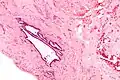

Micrograph showing endosalpingiosis in a lymph node. H&E stain.

Endosalpingiosis is occasionally found in lymph nodes, and may be misinterpreted as an adenocarcinoma metastasis.[5]